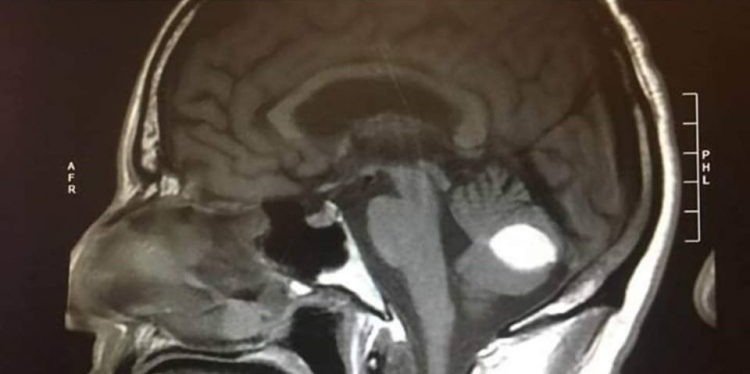

Ảnh chụp não của ông Paul trước và sau khi khối u biến mất. (Ảnh: Paul Wood/Facebook)

Cách đây vài tháng, ông Paul Wood đến từ Lodi, California, Mỹ bắt đầu cảm thấy đau đầu và chóng mặt dữ dội. Các bác sĩ tại Bệnh viện UC San Francisco chẩn đoán Paul bị xuất huyết não, kết quả chụp X-quang cho thấy có một khối u trong não của ông.

Nhưng điều kỳ lạ là một ngày trước khi Paul lên bàn mổ, các bác sĩ phát hiện khối u của ông biến mất. Tất cả đều ngỡ ngàng và không thể giải thích chuyện gì xảy ra. Paul thì tin rằng đó là phép lạ của Thượng đế.